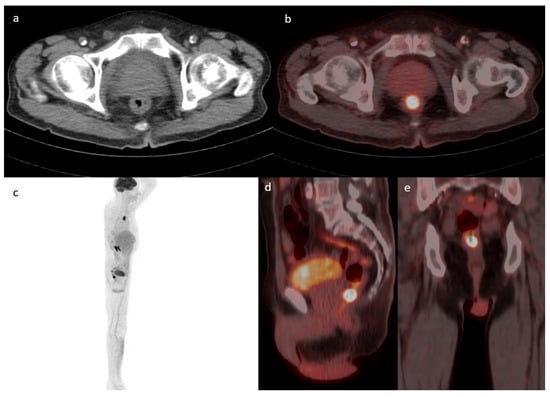

Figure 4 compares the different SUVmax values between three different groups (malignant, pre-malignant, and benign lesions) among patients with focal uptake, with one example of a benign finding presented in Figure 5. Patients with malignant and pre-malignant disease had higher SUVmax with a median of 11.2 (IQR = 9.4, 15.3) and 10.54 (IQR = 6.4, 17.1), respectively, compared to a median of 7.15 (IQR = 5.98, 8) for benign lesions. To assess the role of SUVmax in detecting a truly positive lesion on PET/CT, we used the receiver operating characteristic (ROC) curve. We defined sensitivity as the fraction of occurrence, and specificity as the fraction of absence of cancer/pre-cancer lesions on further investigation with endoscopy. This analysis showed a statistically significant area under the curve of 0.79 (p < 0.0001). An SUVmax of 9.2 had the highest sensitivity and specificity of 0.76 and 0.885, respectively.

Figure 5. Case of a 70-year-old female known to have uterine cervical cancer. Axial CT (a) fused with PET (b) showing a focus of uptake in the distal esophagus with an SUVmax of 5.6. MIP (c)-fused sagittal (d) and axial PET/CT (e) showing increased linear uptake within the distal aspect of the esophagus. The patient underwent gastroscopy, which revealed inflammatory processes in keeping with esophagitis and no evidence of malignancy.